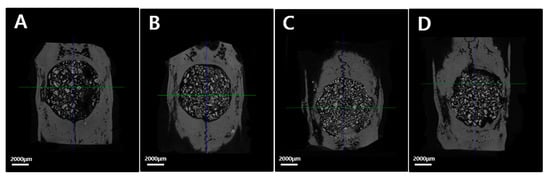

2.2.2. Micro-Computed Tomography (Micro-CT) Findings